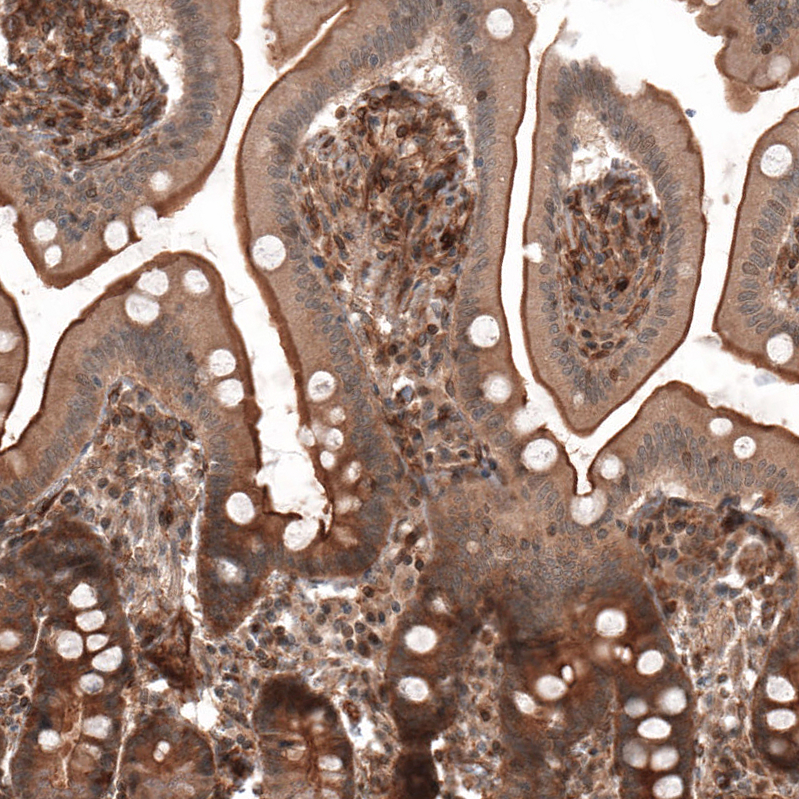

Immunohistochemical staining of human duodenum shows strong membranous positivity in glandular cells.